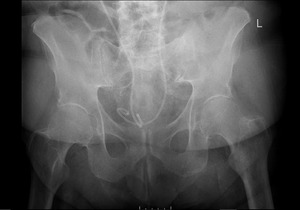

Orthopedics was the first service to evaluate the patient on hospital Day 2 and ordered a CT of the abdomen and pelvis with contrast. This study found that superior to the bladder, there was a 4.9 x 3.8 cm fluid collection with peripheral enhancement concerning for abscess. (Image 2) Internal Medicine then evaluated the patient and reviewed the results of the CT scan. Blood cultures were obtained and the General Surgery service was consulted. A repeat CT with oral contrast was ordered by General Surgery on hospital Day 3. This test showed that the adjacent loops of the intestines along the anterior and superior margin of the fluid collection were partially opacified without obvious extravasation of oral contrast in the region, suggesting fistula (i.e., communication with the bowel). (Image 3)